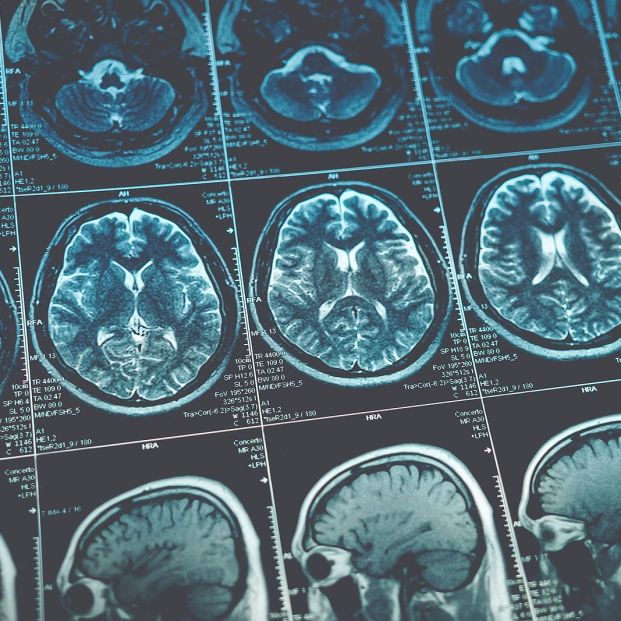

Un estudio del Hospital Universitario 12 de Octubre revela que unas células del sistema inmune predisponen a sufrir patologías como alzhéimer y tumores cerebrales justo a partir de los 57 años, debido a la disfunción de la barrera hematoencefálica que protege el Sistema Nervioso Central.

Esta disfunción estaría causada por el proceso de envejecimiento cerebral que experimenta cambios significativos a esa edad, abriendo la puerta a células inmunitarias defectuosas, ha indicado el centro hospitalario en un comunicado.

En concreto, los análisis moleculares revelaron que tanto la disfunción de la barrera, cuya función es proteger al sistema nervioso del paso de sustancias nocivas, como la integridad de las conexiones neuronales están alterados en el envejecimiento cerebral y son responsables de la progresión de la enfermedad de alzhéimer y los tumores cerebrales.